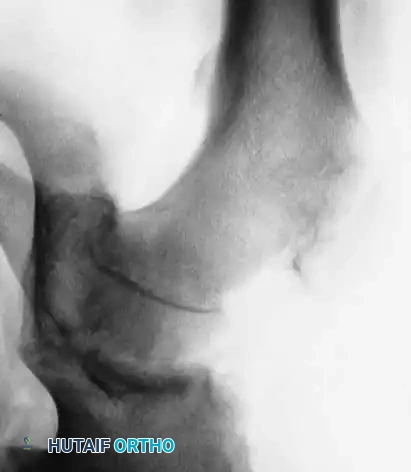

Slipped Capital Femoral Epiphysis (SCFE) represents a unique and complex pediatric hip disorder. While technically a type I transepiphyseal fracture-separation, SCFE is distinguished from standard epiphyseal separations by its distinct natural history, insidious pathogenesis, and biomechanical etiology. The disorder is characterized by the displacement of the proximal femoral epiphysis posteriorly and inferiorly relative to the femoral neck.

The pathogenesis of SCFE is multifactorial, involving a combination of mechanical shear forces and underlying endocrine or metabolic susceptibilities. During the adolescent growth spurt, the physis widens and weakens, making it vulnerable to the increased mechanical loads associated with obesity or rapid growth. Kordelle et al., utilizing three-dimensional computed tomography (CT) analysis in 30 slips, identified significant morphological variations predisposing to SCFE. They noted a reduced femoral anteversion averaging 7 degrees (compared to a normal 12.7 degrees) and a reduced femoral shaft angle of 134.2 degrees (compared to a normal 141 degrees). Furthermore, their analysis confirmed an absence of acetabular remodeling following the slip, underscoring the permanent biomechanical alteration of the joint if left untreated.

* Chronic Slips: Gradual onset of symptoms lasting longer than 2 weeks. Radiographs demonstrate bony healing and remodeling along the posterior and medial femoral neck.

2. Radiographic Severity (Southwick Classification)

Severity is graded based on the degree of displacement relative to the femoral neck diameter or the deviation of the head-shaft angle:

* Mild (Grade I): Displacement < 1/3 of the femoral head diameter, or head-shaft angle deviation ≤ 30 degrees. (Comprises >50% of cases).

* Moderate (Grade II): Displacement between 1/3 and 1/2 of the diameter, or angle deviation between 30 and 60 degrees.

* Severe (Grade III): Displacement > 1/2 of the diameter, or angle deviation > 60 degrees.